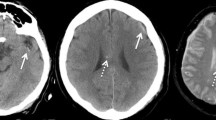

All patients in the study had non-contrast CT scan taken at the admission to hospital. Patients with only post-operative CT scans, CT angiography, or MRI scans were excluded. All available CT images were classified according to the Marshall CT classification system, the Helsinki CT score, and the updated version of NIRIS [27] by two authors (JV, RR). The CT classification systems are described in Table 1.